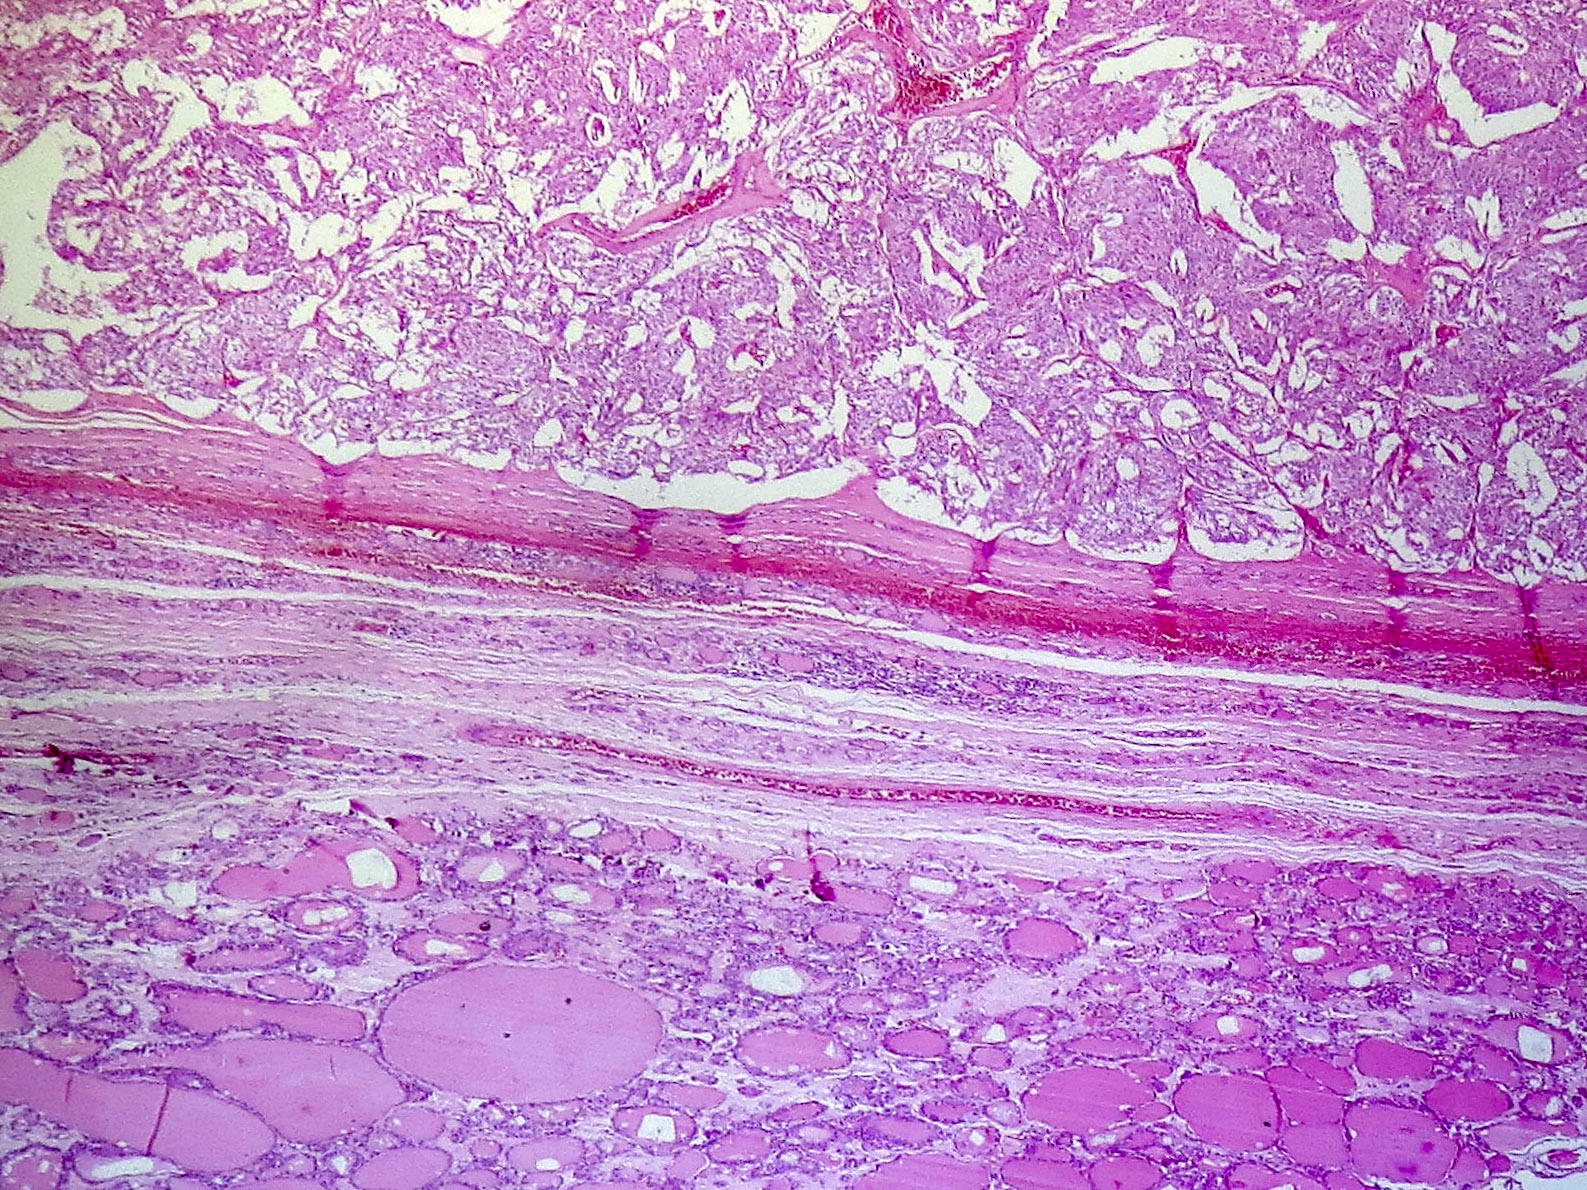

Microscopic (histologic) description

- Wide variety of morphology, can mimic any other thyroid malignancy

- Round, plasmacytoid, polygonal or spindle cells in nests, cords or follicles; often mixtures of these cells

- Stroma has amyloid deposits from calcitonin, prominent vascularity with glomeruloid configuration or long cords of vessels (Am J Surg Pathol 1995;19:642), coarse calcifications, occasional psammoma-like bodies

- Occasionally marked neutrophilic infiltrate, oncocytic tumor cells, papillary patterns

- May entrap follicles

- C cell hyperplasia present in familial but not sporadic cases

Microscopic (histologic) images

Contributed by Shuanzeng Wei, M.D., Ph.D., Joseph Christopher Castillo, M.D. and Mark R. Wick, M.D.